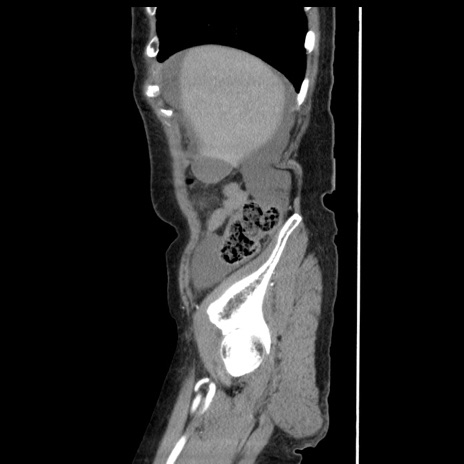

冠状断像

【症例】80歳代女性

【主訴】腹痛

【現病歴】8時間前から腹痛あり来院。

【既往歴】糖尿病、脂質異常症、子宮体癌にて子宮全摘術

【身体所見】意識清明・会話良好だが腹痛で苦悶様、全腹部にわたって反跳痛と圧痛あり

【データ】WBC 13600、CRP 0.14、LDH 224、CK 90